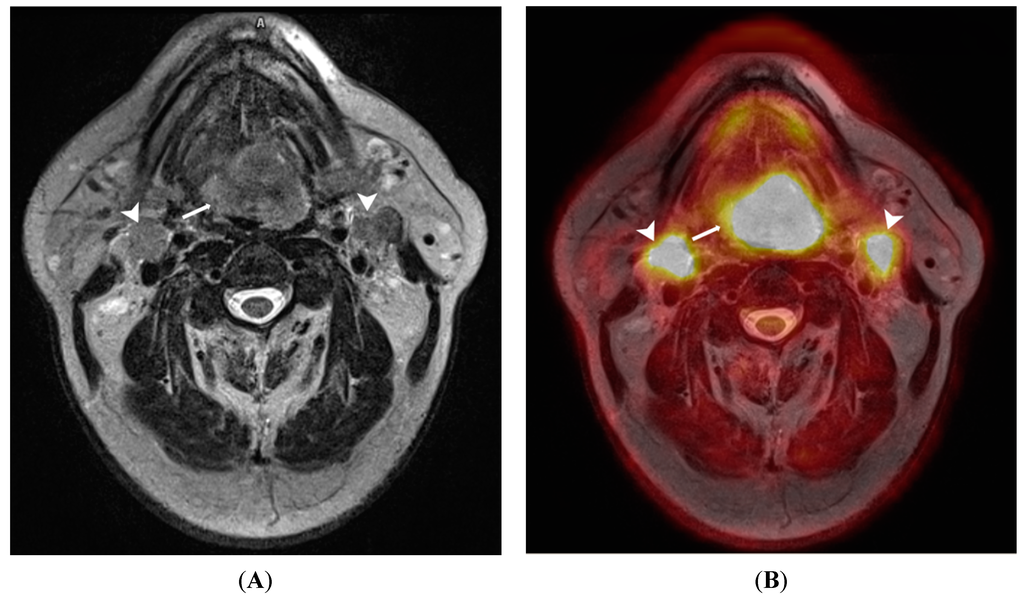

5.1. Head and Neck

- Platzek, I.; Beuthien-Baumann, B.; Schneider, M.; Gudziol, V.; Langner, J.; Schramm, G.; Laniado, M.; Kotzerke, J.; van den Hoff, J. PET/MRI in head and neck cancer: initial experience. Eur. J. Nucl. Med. Mol. Imaging 2013, 40, 6–11. [Google Scholar] [CrossRef] [PubMed]

- Huang, S.-H.; Chien, C.-Y.; Lin, W.-C.; Fang, F.-M.; Wang, P.-W.; Lui, C.-C.; Huang, Y.-C.; Hung, B.-T.; Tu, M.-C.; Chang, C.-C. A comparative study of fused FDG PET/MRI, PET/CT, MRI, and CT imaging for assessing surrounding tissue invasion of advanced buccal squamous cell carcinoma. Clin. Nucl. Med. 2011, 36, 518–525. [Google Scholar] [CrossRef] [PubMed]

- Nakamoto, Y.; Tamai, K.; Saga, T.; Higashi, T.; Hara, T.; Suga, T.; Koyama, T.; Togashi, K. Clinical value of image fusion from MR and PET in patients with head and neck cancer. Mol. Imaging Biol. 2009, 11, 46–53. [Google Scholar] [CrossRef] [PubMed]

- Queiroz, M.A.; Hüllner, M.; Kuhn, F.; Huber, G.; Meerwein, C.; Kollias, S.; von Schulthess, G.; Veit-Haibach, P. Use of diffusion-weighted imaging (DWI) in PET/MRI for head and neck cancer evaluation. Eur. J. Nucl. Med. Mol. Imaging 2014, 41, 2212–2221. [Google Scholar] [CrossRef] [PubMed]